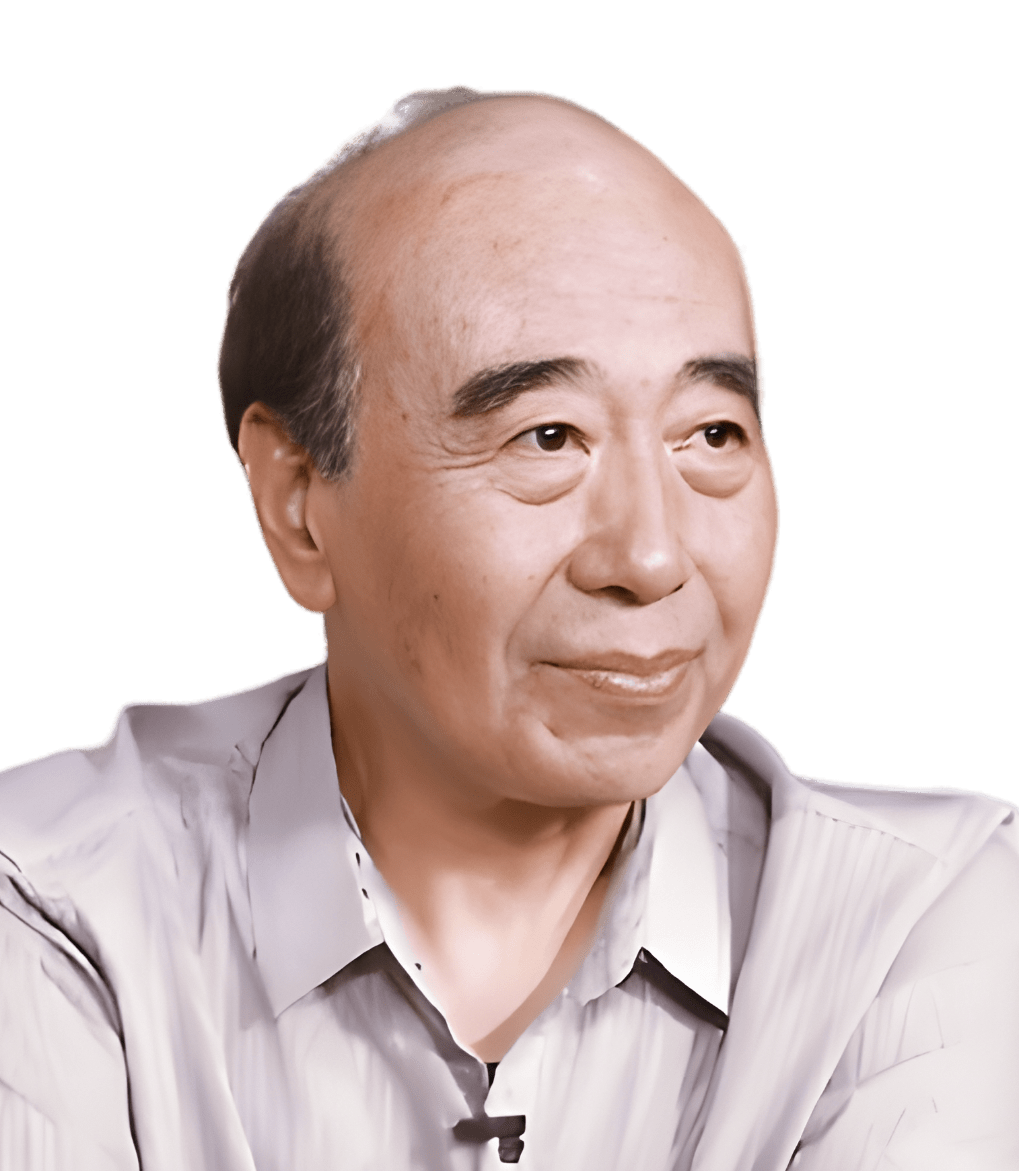

伍沪生

- 中国老教授协会医药专业委员会骨质疏松与骨关节病专家组主任

- 北京医学会风湿病学分会顾问

- 北京医师协会风湿免疫科医师分会常委

- 海峡两岸医药卫生交流协会风湿免疫病学专业委员会顾问

- 中国营养学会会员,注册营养师